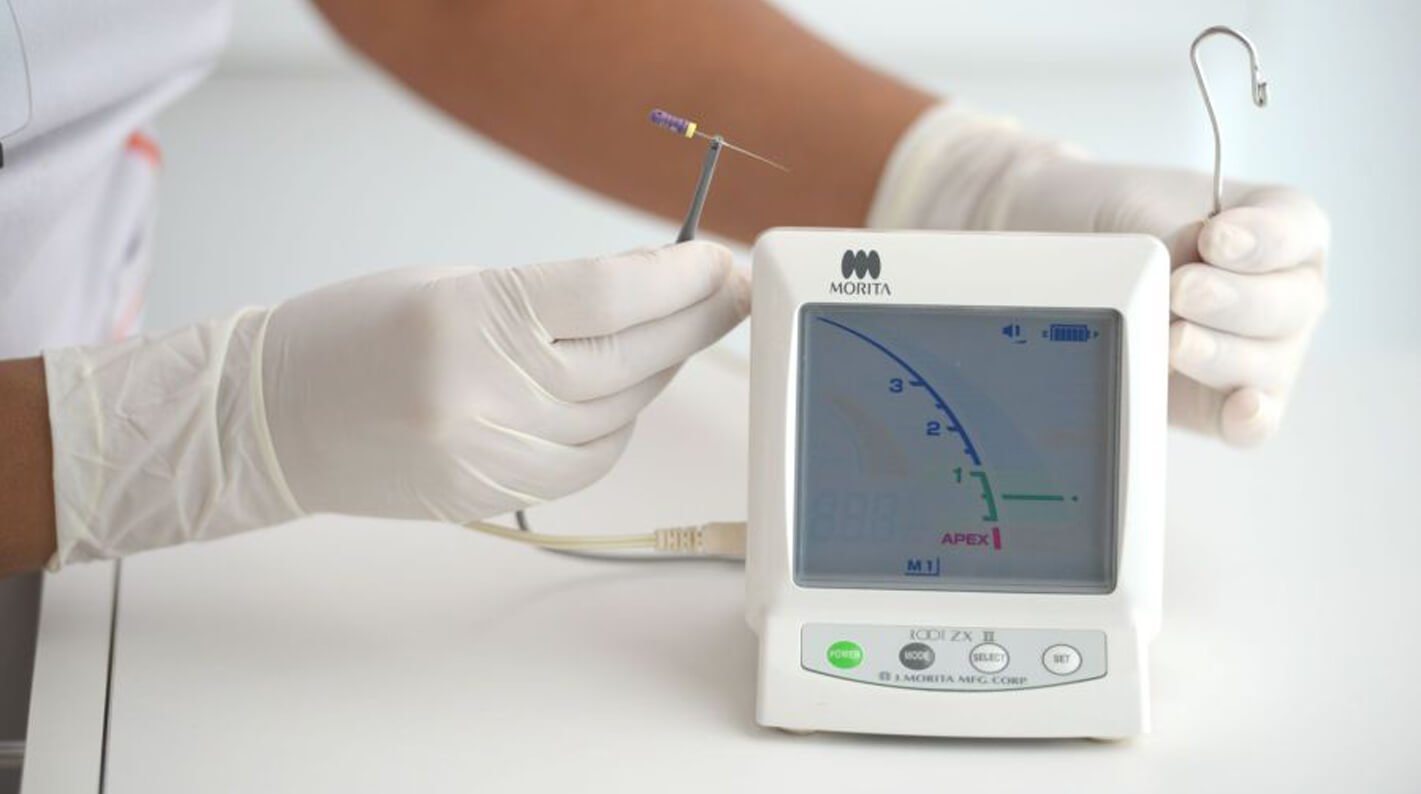

En la Clínica Mompell & Micó, sabemos que el primer paso para ofrecerte el mejor tratamiento es un diagnóstico completo y preciso. Con tecnología avanzada y un equipo especializado, aseguramos que cada detalle sea considerado para ofrecerte el mejor plan de tratamiento personalizado.